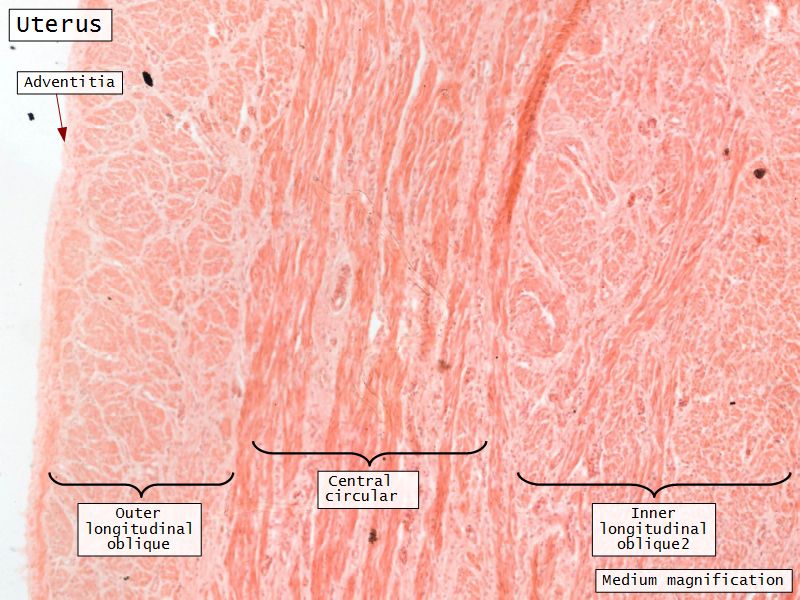

Myometrium

- 3 layers indistinct smooth

- Inner longitudinal/oblique

- Central circular

- Large blood vessels

- Stratum vasculare

- Outer longitudinal/oblique

Adventitia

- Or serosa

- Covers myometrium